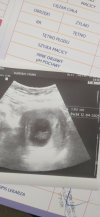

Otóż tak .. termin na 12 kwiecień i lekarz tylko ten termin bierze pod uwagę z USG . Lekarz włączył leczenie euthyroxem ( sorry jak coś przekrecilam) dawka 25 . Dostałam skierowanie na badania prenatalne.. dzidzia rośnie , było widać serduszkoi jak i jak?

Aaaa .. i dostałam skierowanie do poradni diabetologicznejOtóż tak .. termin na 12 kwiecień i lekarz tylko ten termin bierze pod uwagę z USG . Lekarz włączył leczenie euthyroxem ( sorry jak coś przekrecilam) dawka 25 . Dostałam skierowanie na badania prenatalne.. dzidzia rośnie , było widać serduszkonadrobiliśmy 2 dni

8 + 3 dni .. crl 1.93 cm